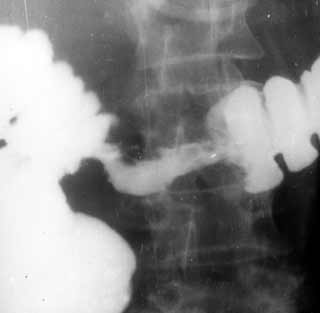

Рентгенологическая визуализация стенозов толстой кишки.

Рис. 4. Рак толстой кишки.